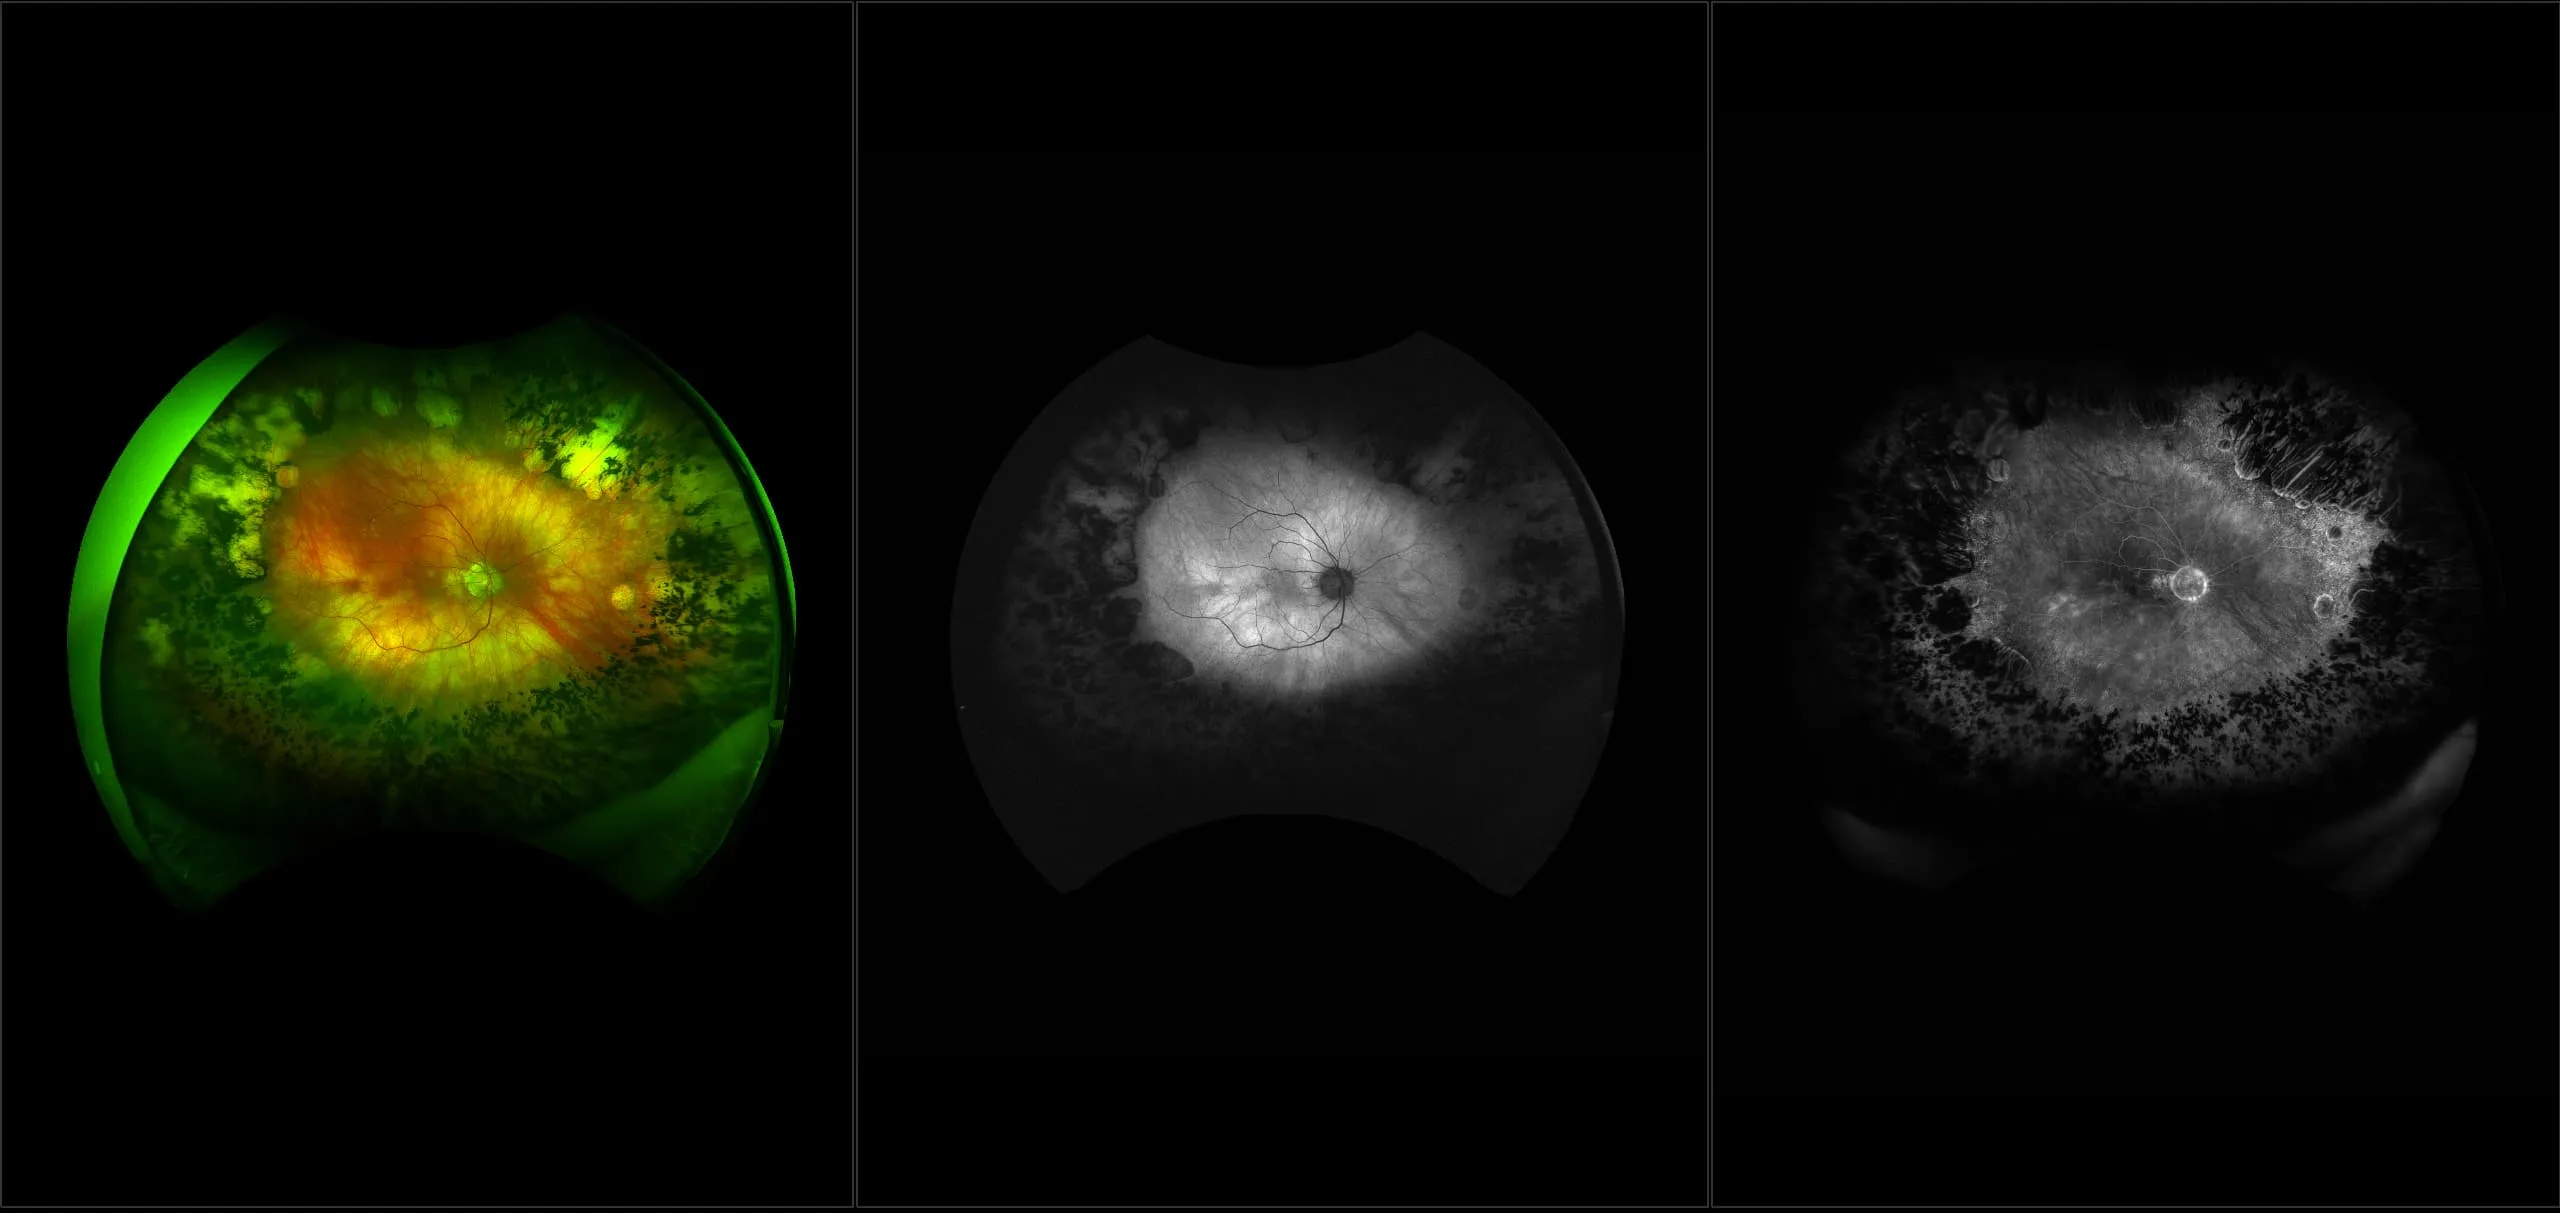

optomap® Recognizing Pathology

This material is designed as a searchable reference resource to support clinical decision-making. The information contained here should be used as general guidance when viewing optomap and OCT images from Optos devices. The differential diagnosis should be made under the direction of the responsible physician. These images were taken on the latest ultra-widefield optomap devices.

The Cases and Images

optomap Recognizing Pathology is searchable by pathology and/or optomap image modality. You may search by multiples of each selection. Each individual case is represented by the accompanying thumbnail image. Most cases include several different optomap image modalities. To view a full description of the case, please click on the thumbnail. Each image in the case will be made available through our OptosAdvance software which provides multi-dimensional visualization of digital images to aid in the analysis of anatomy and pathology. Support and pathology definitions can be found by selecting one of the buttons, above. Should you have questions, please complete the form below.